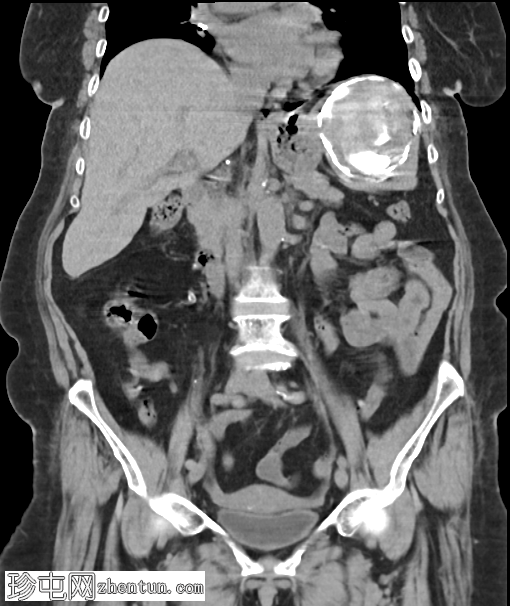

CT

1.png

轴位

平扫

脾脏内可见一边界清晰的低密度囊性病变,可见边缘及内部钙化。

胆结石。